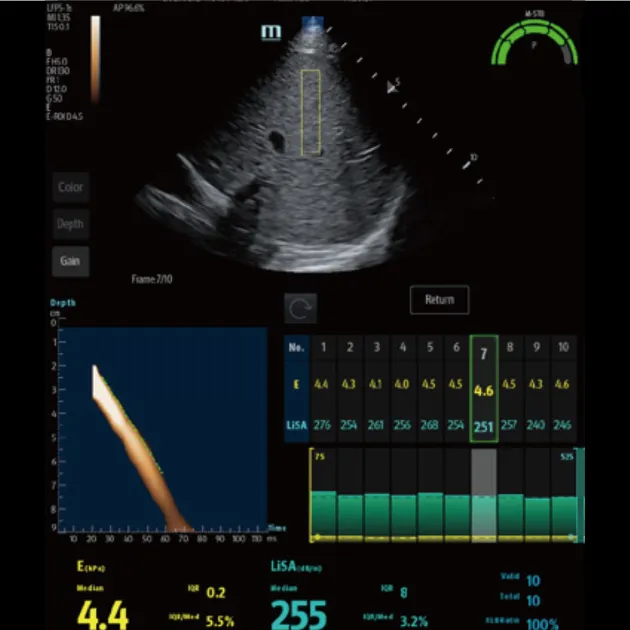

Advanced ViTE (визуализированная транзиторная эластография)

- Проводить количественное выявление и оценку фиброза и стеатоза печени под визуальным контролем 2D-ультразвука в режиме реального времени

- Позволяет избежать образования кровеносных сосудов и повреждений, повысить точность и достоверность измерения

- Значительно снижает сложность операции, повышает точность и повторяемость количественных измерений

Быстрое интеллектуальное получение данных Q-сканирования

- Нажатием одной кнопки можно автоматически и непрерывно получать 10 групп эффективных данных и проводить интеллектуальный анализ

- Точные и достоверные результаты обнаружения могут быть получены немедленно, всего через 7 секунд после позиционирования

Надежный показатель контроля качества

- Индекс давления (P): качественный контроль давления зонда

- Индекс стабильности движения (m-STB): обеспечивает стабильность дыхания

- Четкая индикация с другим цветом для улучшения контроля качества во время обследования